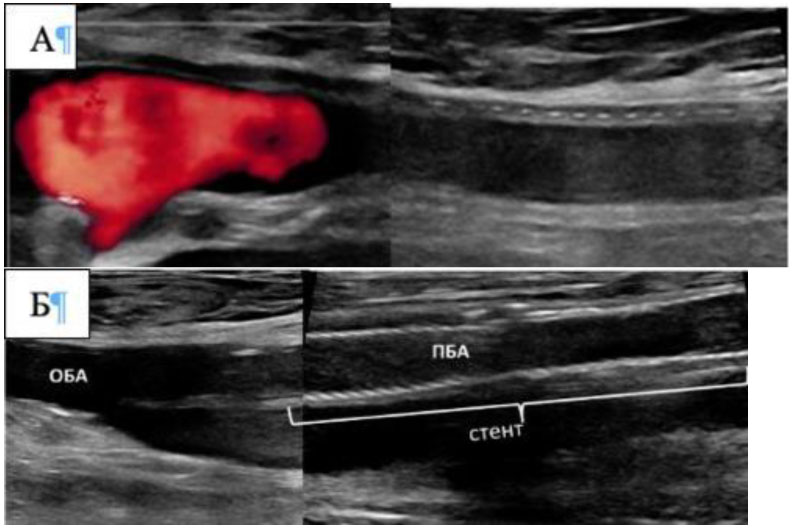

При определении тактики хирургического лечения очень важна структура тромбоза, которая коррелирует с его давностью. Структура поражения оценивается в В-режиме. Свежие тромбозы артерии визуализируются, как гипоэхогенные массы (рис. 2), которые могут формироваться на эхопозитивных пристеночных атеросклеротических бляшках.

Рис. 2. Относительно свежие тромбозы. А - тромбоз бедренно-подколенного шунта (гомогенная, гипоэхогенная структура тромба). Б - гипоэхогенный, гомогенный тромбоз стента ПБА.